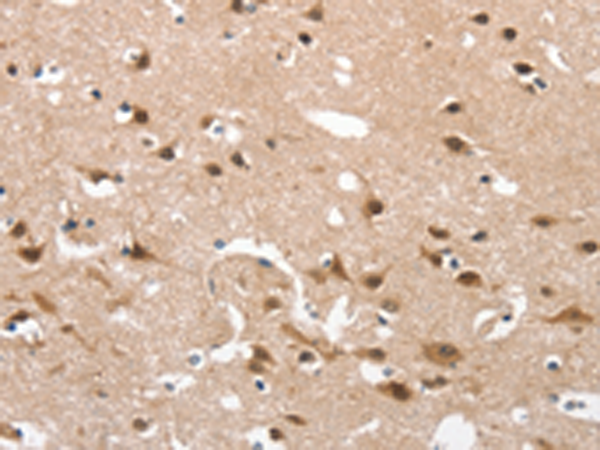

- The image is immunohistochemistry of paraffin-embedded Human brain tissue using P04339(CD163 Antibody) at dilution 1/30. (Original magnification: ×200)